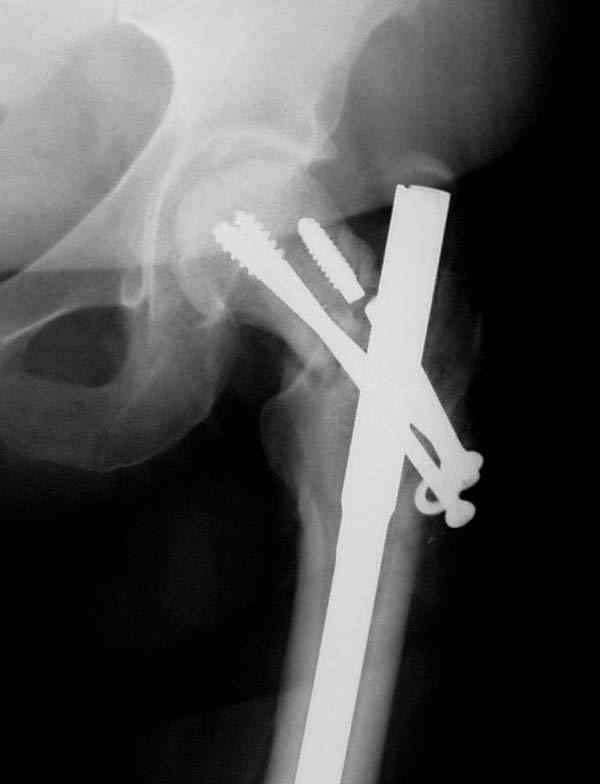

Имя     : missed neck postop.JPG

Имя     : ipsilateral neck shaft.JPG

Имя     : ipsilateral neck shaft nonunion.JPG